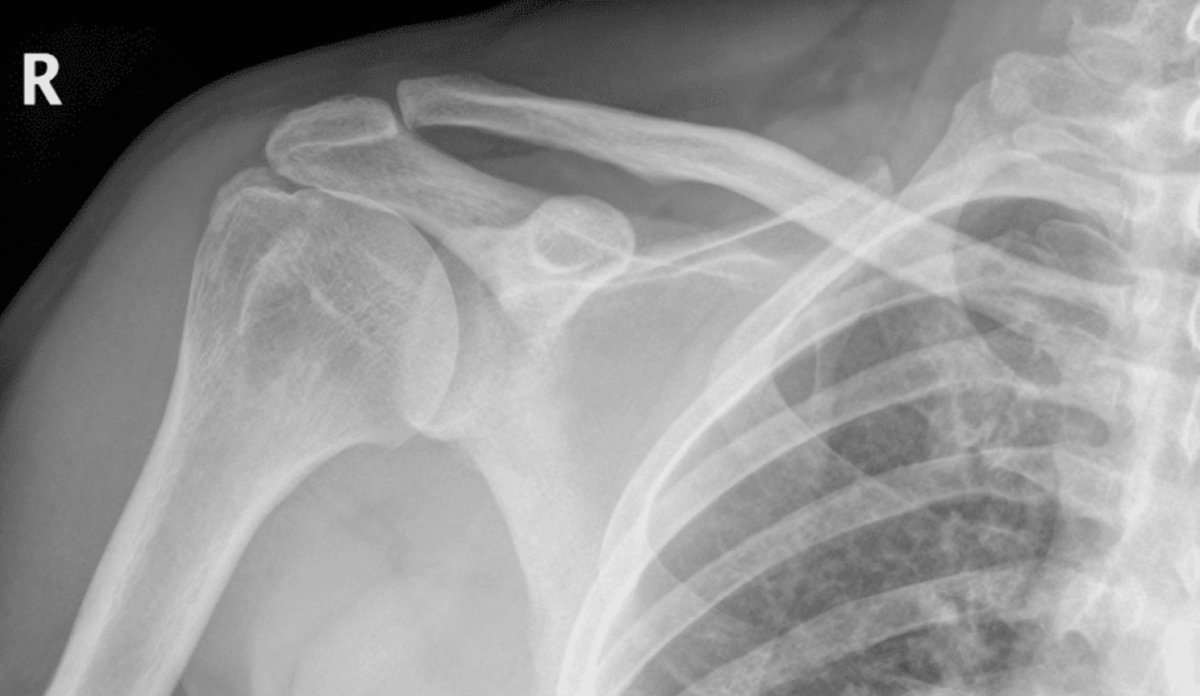

We worked to connect him with a proper doctor, an orthopedic specialist, who ordered an MRI revealing a torn rotator cuff. A month later, his surgery was approved, and his extensive rehabilitation process began.